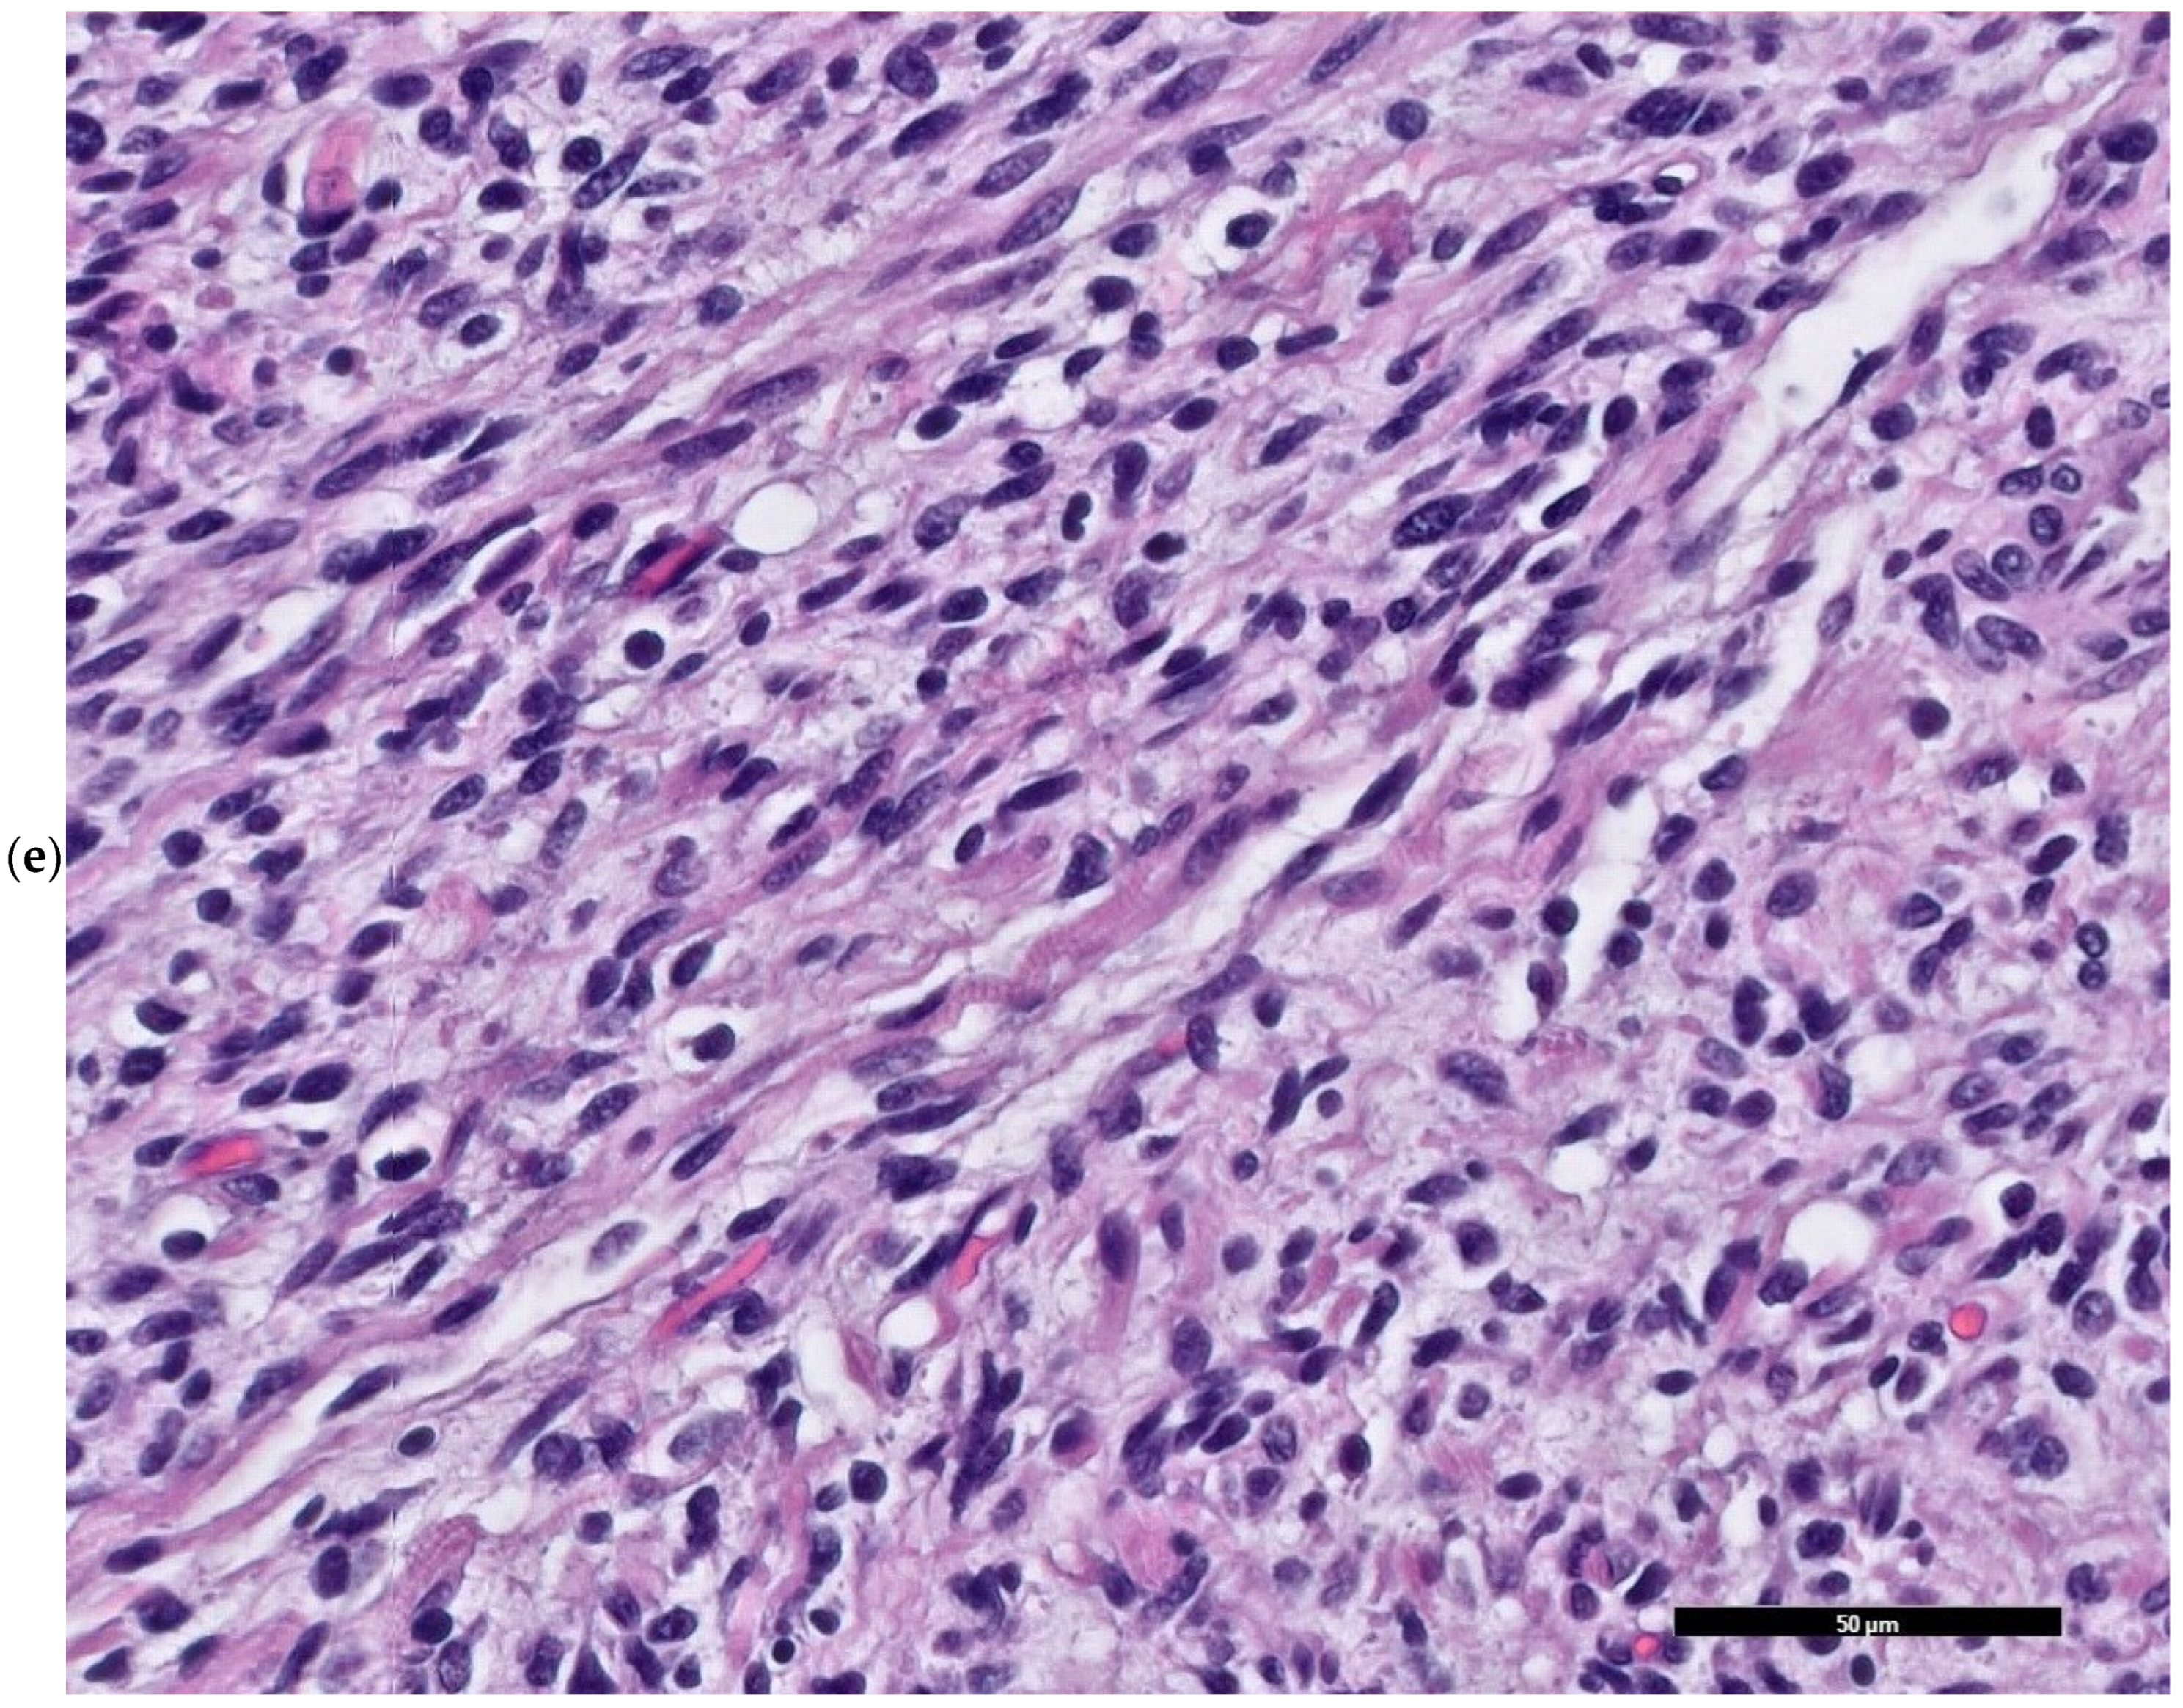

2. Case Presentation